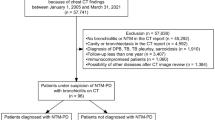

The study was based on institutional data on NTM infections over 2 years (2016 and 2017). The diagnosis of NTM infection was established locally and the culture confirmed by the National Mycobacteria Reference Laboratory of the Croatian National Institute of Public Health (CNIPH) in Zagreb. Samples for culturing were obtained via bronchoalveolar lavage (BAL), aspiration from bronchi with a catheter and/or in sputum with PCR/DNA based methods. A total of 131 persons with positive NTM cultures were identified, of which 56 did not have available CT scans and therefore were excluded from the study. Patients with disseminated malignant disease (n = 7), lymphoproliferative disorders (n = 3), and established sarcoid (n = 2) were also excluded from the study. There were no patients with HIV infections or other immunosuppressive disorders.

Finally, the study included 63 patients, all of which had CT done around the time of diagnosis in our institution (within 1 month). As there was no CT protocol in place for NTM infections, different protocols for CT scanning were used: usual chest CT with or without i.v. administration of contrast agent, CT pulmonary angiogram and HRCT. There were also multiple CT scanners involved (Siemens Healthcare, Erlangen, Germany and General Electric devices Boston, MA, USA). Therefore, scanning parameters varied. The slice thickness was 1 mm or 1.25 mm. The images were analyzed on standard picture archiving and communication system (PACS workstation).

The radiologic findings in 63 patients diagnosed with a pulmonary infection caused by NTM were analyzed (40 men and 23 women; mean age 63 years; age range 11–85 years).

For this study, only nodular patterns of lung infection were assessed in detail. Of the 63 patients included in the study, nodules were detected in 51 (81%). The centrilobular nodular pattern was detected on 25 (39.8%), perilymphatic on 7 (11.1%), and random on 6 occasions (9.5%).

There were 13 (20.6%) patients with combined nodular patterns. In three patients all nodular patterns were detected at the same time point but confined to smaller areas in different lung regions. Furthermore, 10 patients were found to have 2 synchronous nodular patterns in different combinations: centrilobular with perilymphatic (n = 5) and centrilobular with random (n = 5). Interestingly, no patient was identified with a combination of perilymphatic and random nodular distribution patterns.

As per distribution of each nodular pattern concerning NTM species, there was a significant difference between Mycobacterium avium complex (MAC: M. avium and M. intracellulare), M. fortuitum and other NTM (M. abscessus, M. chimerae, M. malmoense, M. celatum, M. kansasii, M. segmatis) (Fig. 1).

The proportion of NTM species in the created group (centrilobular, perilymphatic, random, combined pattern and no nodules group). MAC patients with identified M. avium and M. intracellulare complex, Other NTM patients with identified M. abscessus, M. chimerae, M. malmoense, M. celatum, M. kansasii or M. segmatis

In the MAC group (n = 20) 14 cases of centrilobular and a single case of random nodule pattern were detected. Interestingly, there were no cases of perilymphatic or combined nodule pattern in this group.

The distribution of nodular patterns was significantly different between MAC and non-MAC groups (Fisherʼs 2 × 5 exact test, p = 0.0006). The centrilobular pattern was the most responsible for the deviation (because the expected number of cases was 7.9, and the observed number of cases was 14). This was further confirmed by comparing the distribution of the centrilobular pattern versus other patterns in MAC and non-MAC groups by Fisherʼs exact 2 × 2 test (p = 0.0019).

Similarly, in the NTM group without MAC (n = 43), 11 cases of centrilobular, 7 perilymphatic and 5 random nodule distribution patterns were found. All of the 7 perilymphatic and 15 combined nodule patterns were detected in non-MAC group while the expected values were 4.8 and 8.9 indicating these patterns also influence the overall significance of the distribution. Indeed, when comparing the distribution of combined pattern versus other patterns in MAC and non-MAC groups the distribution was statistically significant (Fisherʼs exact test 2 × 2, p = 0.0057).

The distribution of different patterns in patients with M. fortuitum was also significantly different from those of patients without M. fortuitum (Fisherʼs 2 × 5 exact test, p = 0.0009). The pattern of random nodules was detected in 5 cases of infections caused by M. fortuitum, while the expected value was 1.1 indicating that this finding was the most responsible for the observed deviation. This was confirmed by Fisherʼs exact 2 × 2 comparison of the distribution of random pattern versus other patterns in M. fortuitum vs. other groups (p = 0.0004).

The distributions of different patterns in patients infected with the more common M. xenopi (n = 15) were not statistically different from patients without those NTM; however, the distribution of patterns in patients infected with all other NTM species combined as a group (M. abscessus, M. chimerae, M. malmoense, M. celatum, M. kansasii, M. segmatis) was borderline significantly different (Fisherʼs 2 × 5 exact test, p = 0.0455). The perilymphatic pattern was mainly responsible for this deviation as the expected value was 0.9 and 3 cases were observed. Comparing the perilymphatic vs. other patterns in patients infected with other NTM group also indicated some statistical significance (Fisherʼs 2 × 2 exact test, p = 0.0379).